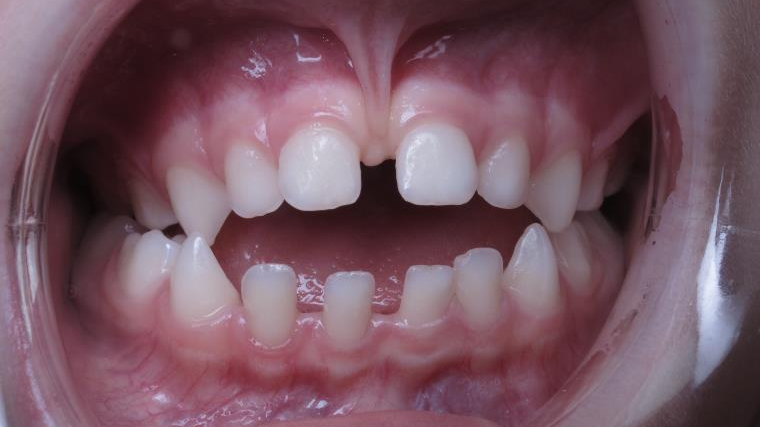

appareillage mobile pendant 3 ans

sectionnel multibagues pendant 8 mois

surveillance évolution de la dentition

bilan de début et en cours de traitement